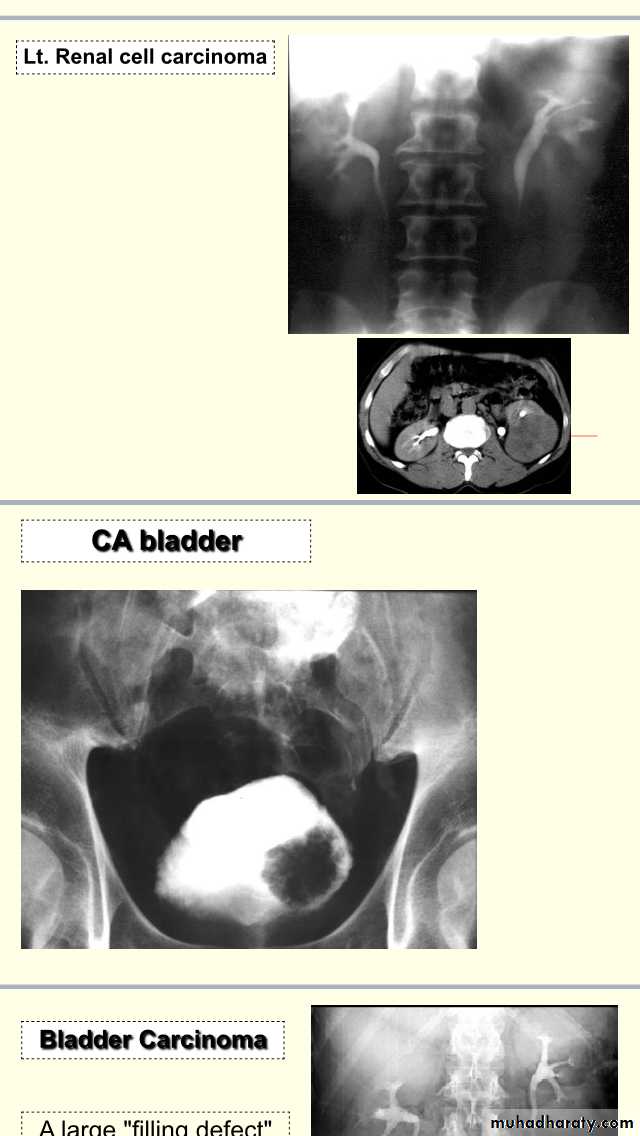

IVU Cystogram phase :- filling defect in the lt lateral side of the bladder DDX:- stone,tumour, blood clot,bladder mass, fungal ball,F.B”catheter part”.

Cystogram IVU ,time predicted <30min,irregular filling defect in the lt side of bladder.